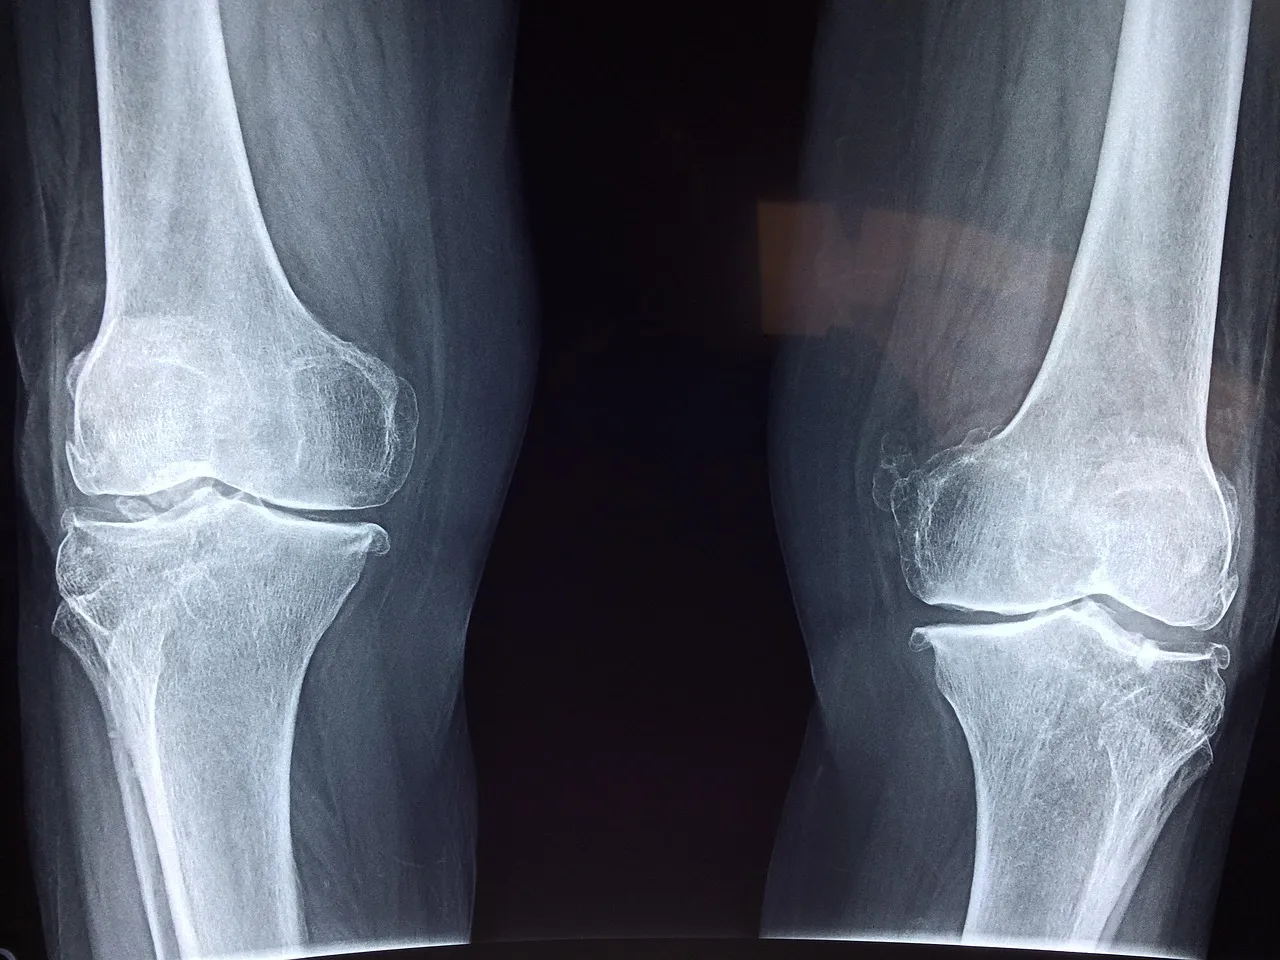

Veelvoorkomende Signalen van Verminderde Mobiliteit

Gewrichtsgeluiden

Kraken, knarsen of knappen – het klinkt alarmerend, maar is niet altijd zorgelijk. Toch kan het een teken zijn dat kraakbeen minder soepel is of dat er kleine luchtbelletjes in het gewricht ontstaan. Als het gepaard gaat met pijn, is het verstandig om hier meer aandacht aan te besteden.

Verminderde Flexibiliteit

Merk je dat je niet meer zo gemakkelijk bukt, hurkt of draait? Dat je schoenen aandoen lastiger wordt? Dit zijn signalen van verminderde mobiliteit in heup-, knie- en enkelgewrichten. Het kan te maken hebben met spierspanning, maar ook met de kwaliteit van je gewrichtsweefsel.

Pijn Bij Belasting

Pijn die optreedt bij traplopen, bukken of tillen is een duidelijk signaal. Het hoeft niet altijd een blessure te zijn – het kan ook wijzen op overbelasting, ontstekingen of een gebrek aan voedingsstoffen die gewrichtsstructuren ondersteunen.